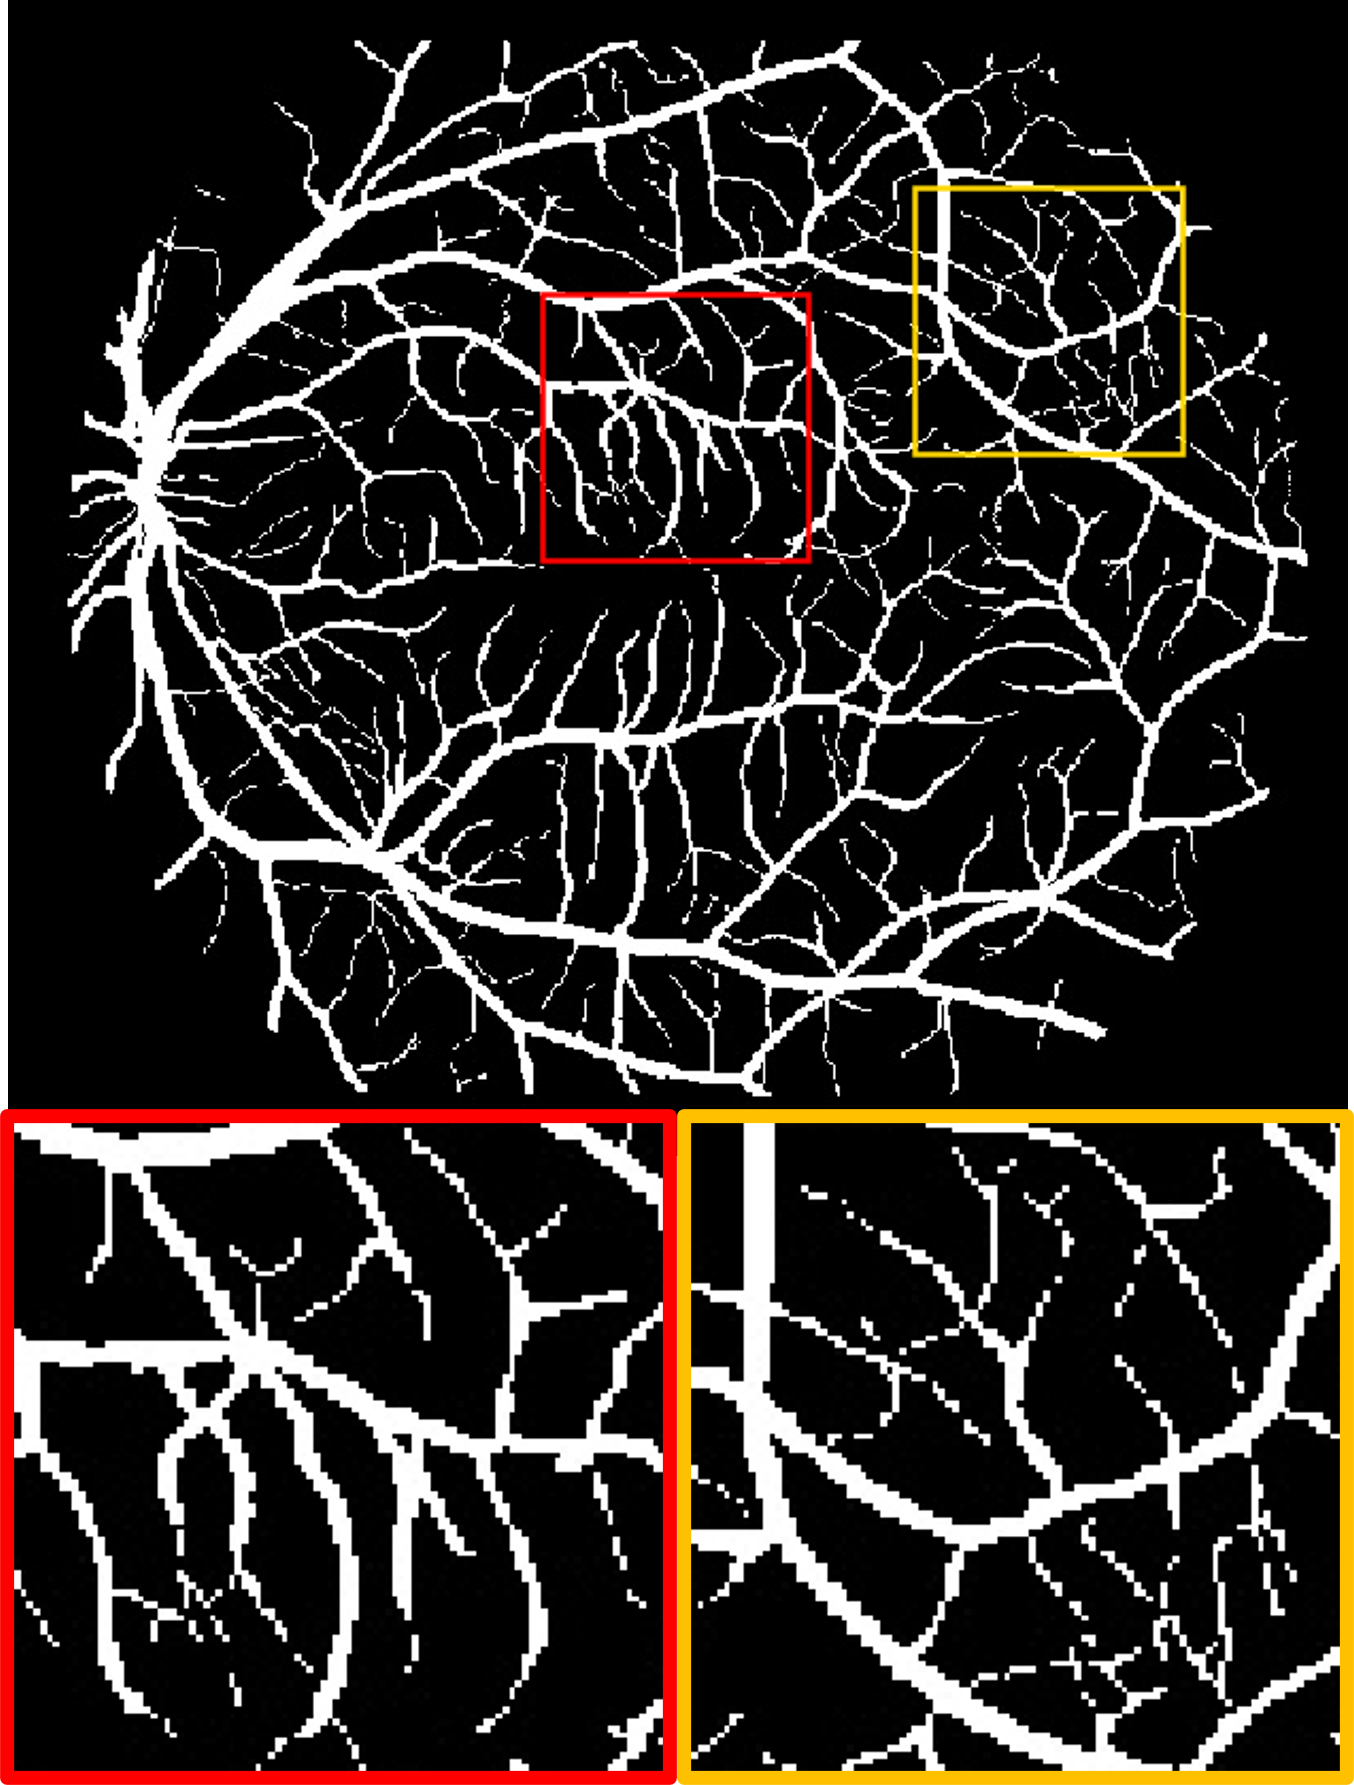

Datasets. We use four publicly available fundus datasets as shown in Fig. 1(b). The DRIVE dataset [15] consists of 20 labelled images of size . The HRF dataset [16] contains 45 labelled images of size . The STARE dataset [17] includes 20 labelled images of size . The ARIA dataset [18] includes 138 labelled images of size . DRIVE and HRF are set as source domain, whereas STARE and ARIA are used for testing.

Fig. 2 shows a test example from each of the target domains. We observe that for different datasets, the manual annotations includes varying amounts of detail: the label for the STARE dataset contains many more small vessels than ARIA. In the ARIA example, the deep angiogram is able to enhance the thin vessels with very poor contrast. This is also evident by the big vessels seen at the bottom left quadrant of the image where the illumination is low. Moreover, the angiogram filters out the circular artifacts seen within the red box. In the STARE example, our model extracts most of the vasculature including the faintly visible fine vessels. These tiny vessels have relatively lower intensity in the deep angiogram, which suggests lower confidence. Compared to the manual label, the deep angiogram can also delineate the vessel diameter more precisely.